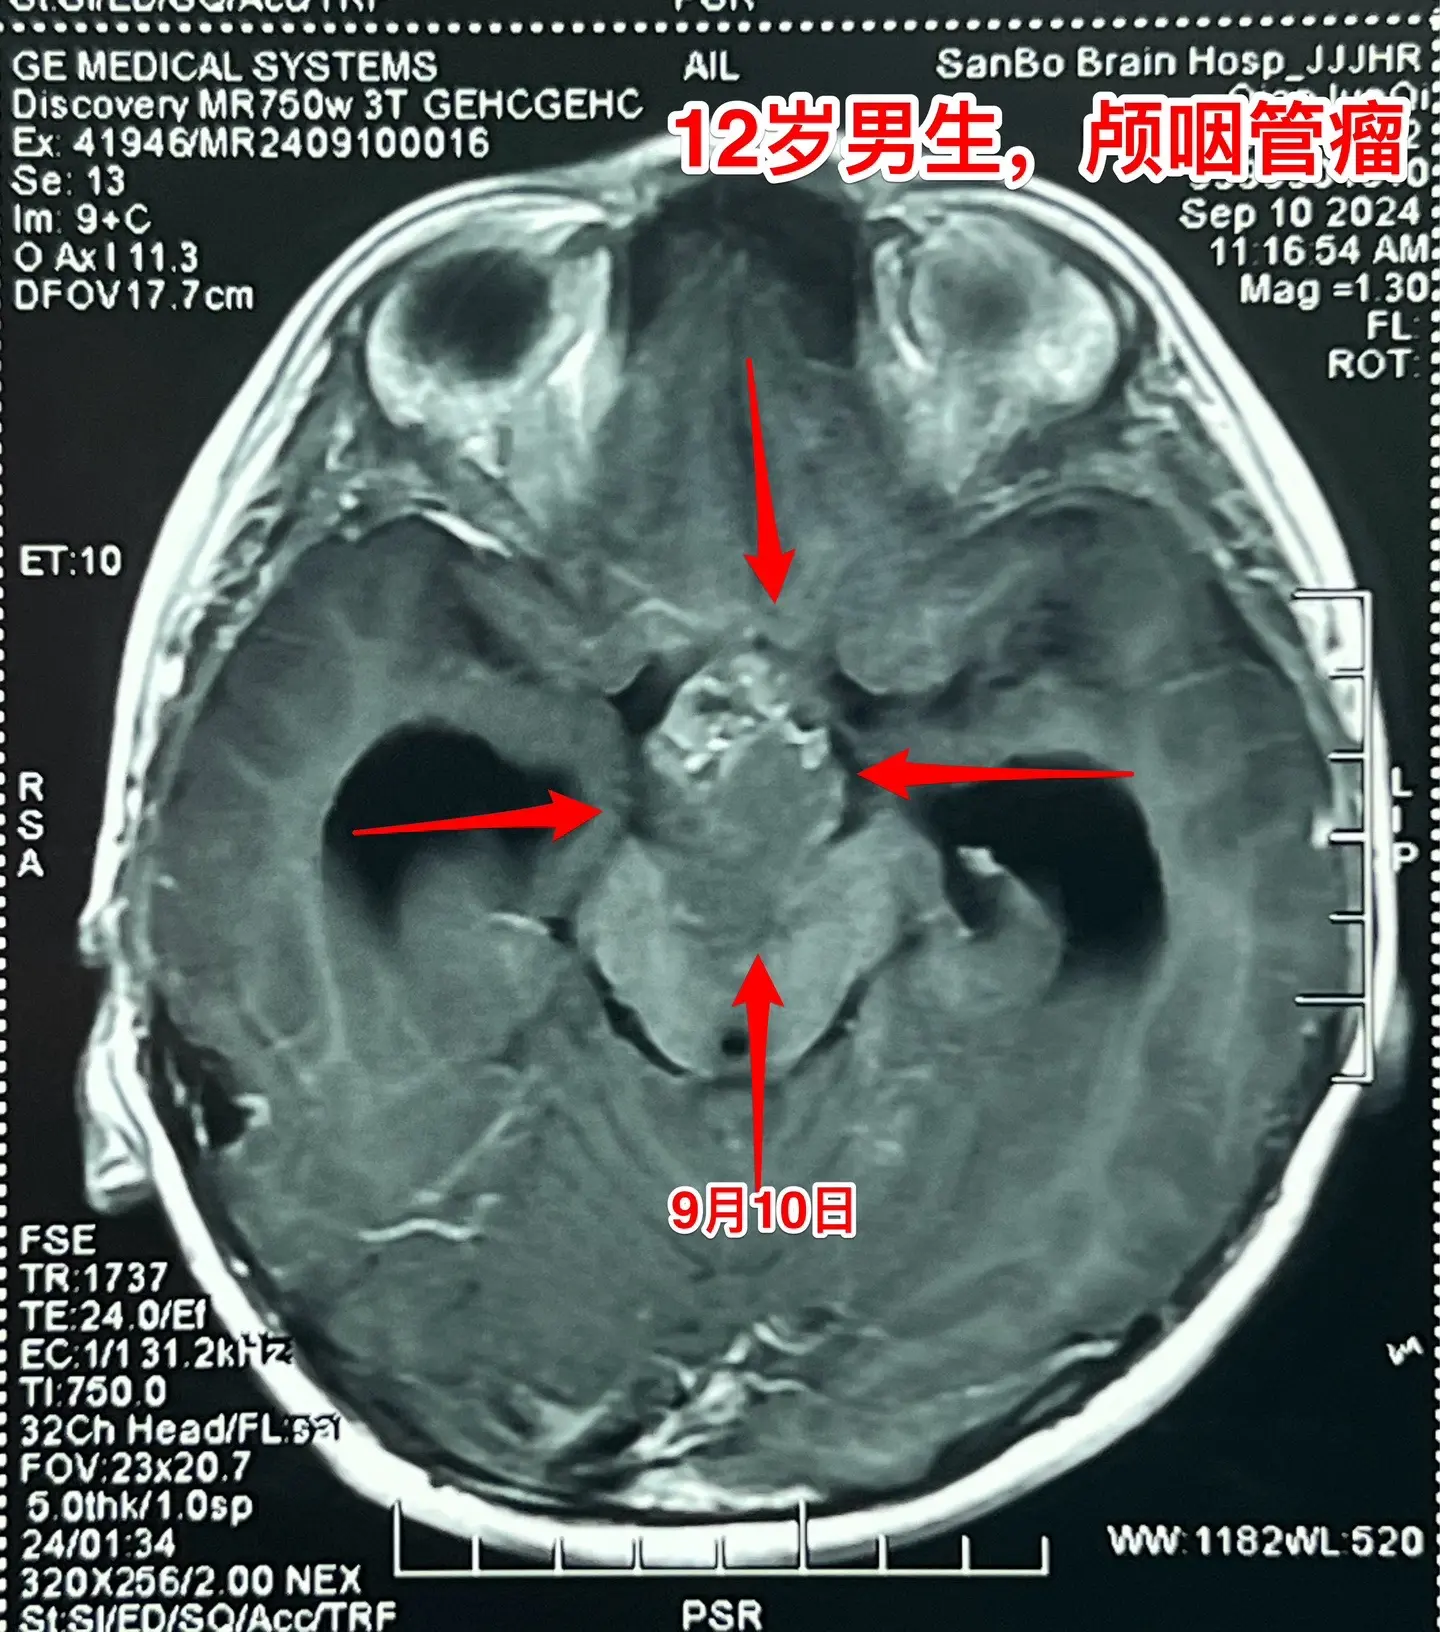

12岁南京男孩子头痛、呕吐。平时感觉身体很好,9月7日因头痛、呕吐到医院检查发现脑部长了颅咽管瘤,并且有脑积水。 9月9日到我院住院。住院时头痛、呕吐症状减轻了。复查磁共振显示颅咽管瘤的形态稍有变化,脑积水似乎有减轻。测视力发现他的视力有下降。这个颅咽管瘤生长的时间预计有两年时间,患儿症状不严重,最终因脑积水出现头痛、呕吐症状才发病。仔细检查还是可以发现一些蛛丝马迹,比如视力下降。颅咽管瘤有时会自动变小,很可能是肿瘤囊破裂了。囊变小了,脑积水就减轻了,头痛、呕吐症状就减轻了。 9月19日行开颅手术,将颅咽管瘤完全切除。手术后患者感觉视力有好转。希望肿瘤永不复发。